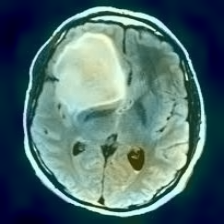

Figure 1: Heatmap Comparison of Unhealthy Images. Different columns show unhealthy MRI images of different positions, sizes, and textures. The first row is the raw image. The second row is the heatmap predicted with PatchCore. The third raw is the heatmap predicted with the proposed method.